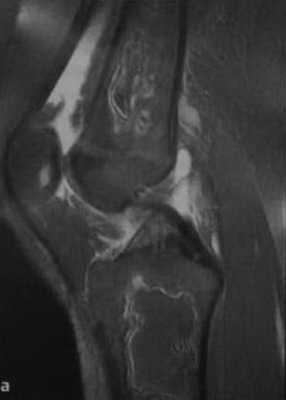

а, b Инфаркт зрелого костного мозга. (а) Сагиттальная протонная плотно-взвешенная МРТ с подавлением МР-сигнала от жировой ткани. Изображение демонстрирует гирляндовидный склеротический край и центральный участок с сигналом жирового костного мозга. Множественные некротические зоны расположены преимущественно в метадиафизальной области, однако несколько находятся непосредственно рядом с суставом, в связи с чем имеется риск уплощения суставных поверхностей;

![Снимки МРТ и КТ. Инфаркт кости]()

b) Рентгенологическое исследование демонстрирует выраженный склеротический край и центральный участок снижения рентгенопрозрачности в дистальном отделе бедренной кости и в большеберцовой кости. Проксимальный отдел бедренной кости демонстрирует участок частичного грубого склероза, который иногда трудно отличить от энхондромы.